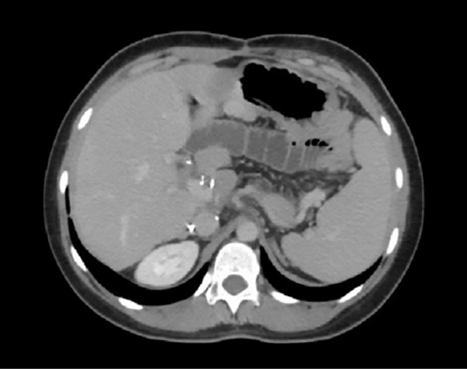

Figures 1. A. and B. Contrast-enhanced abdominal computed tomography in the portal phase, corresponding to post–liver transplant follow-up studies.